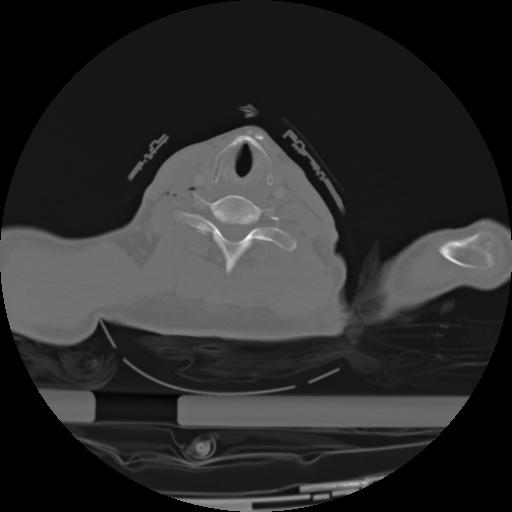

21 ANGIO,CE,Axial,3.0,ANGIO,,